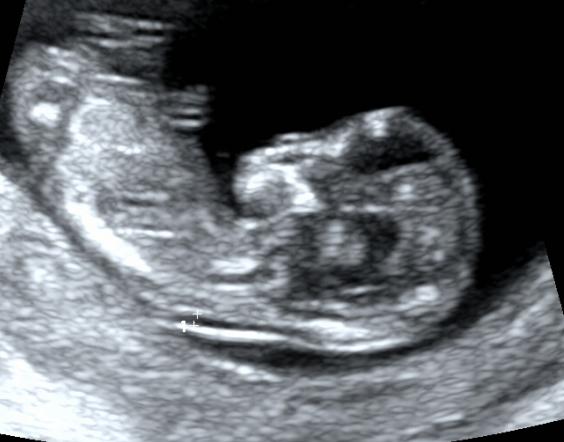

手手脚脚都能看到一些。

甚至有时还能看见TA在肚子里舞蹈。

上图就是一个两脚朝天,此时我们可以在这个切面观察TA 的股骨长,股骨长的测值也可以作为矫正孕周的一个重要参数。